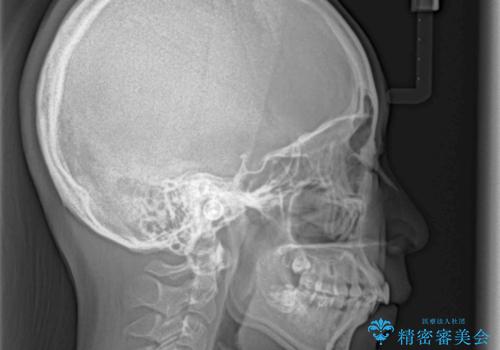

- 咬み合わせと口元の突出感を気にして来院された患者様です。

上顎に対して、下顎が後方にある咬み合わせであるため、上顎左右小臼歯のみの抜歯か、下顎左右小臼歯も抜歯とするのか悩むところでした。

まずは上顎のみ抜歯を行って矯正治療を進め、下顎小臼歯も抜歯が必要となれば速やかに抜歯することとしました。

上顎抜歯のみでは奥歯の咬み合わせを改善することが困難であったため、途中で下顎小臼歯も抜歯をしました。

抜歯のタイミングが遅れると治療期間が長期化するため、速やかに抜歯の判断をし、2年強の期間で治療を終えることができました。